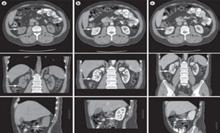

Un total de 49 de pacienți care s-au prezentat la camera de garda a Spitalului Clinic de Urgență „Sfântul Ioan” București cu patologie renală acută sugerând prezența unor calculi la nivel renal și/ sau ureteral care au fost confirmați prin imagistică (radiografie), ultrasonogra-

fie sau computer tomografie) (Fig.1) au fost incluși în acest studiu retrospectiv, în perioada septembrie 2021 – decembrie 2021. Toți pacienții selectați au avut indicație de intervenție de urgență și au fost tratați prin inserarea unui stent dublu J. Am analizat rata de stone-free după a doua intervenție, care a fost una dintre următoarele: ureteroscopie semirigidă,

Fig. 1. Poziţionarea mai multor pietre în scanarea CT cu sau fără substanță de contrast.

Fig. 2 Imagini CT cu substanță de contrast cu litiază renală stângă și hidronefroză Fig. 3 Rata Stone Free - Comparație între cele 4 grupe de pacienți